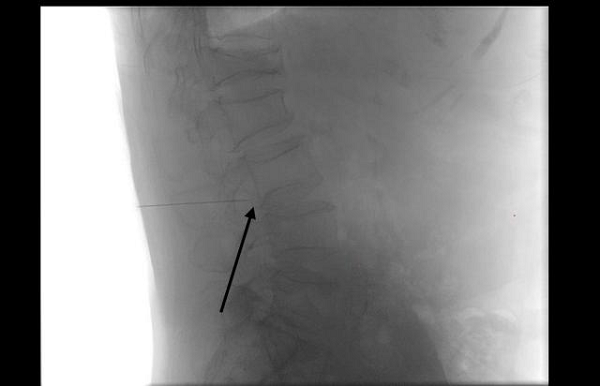

图:医生在影像引导下,精准定位病灶

图:细针穿刺至受压神经根,进行精准给药